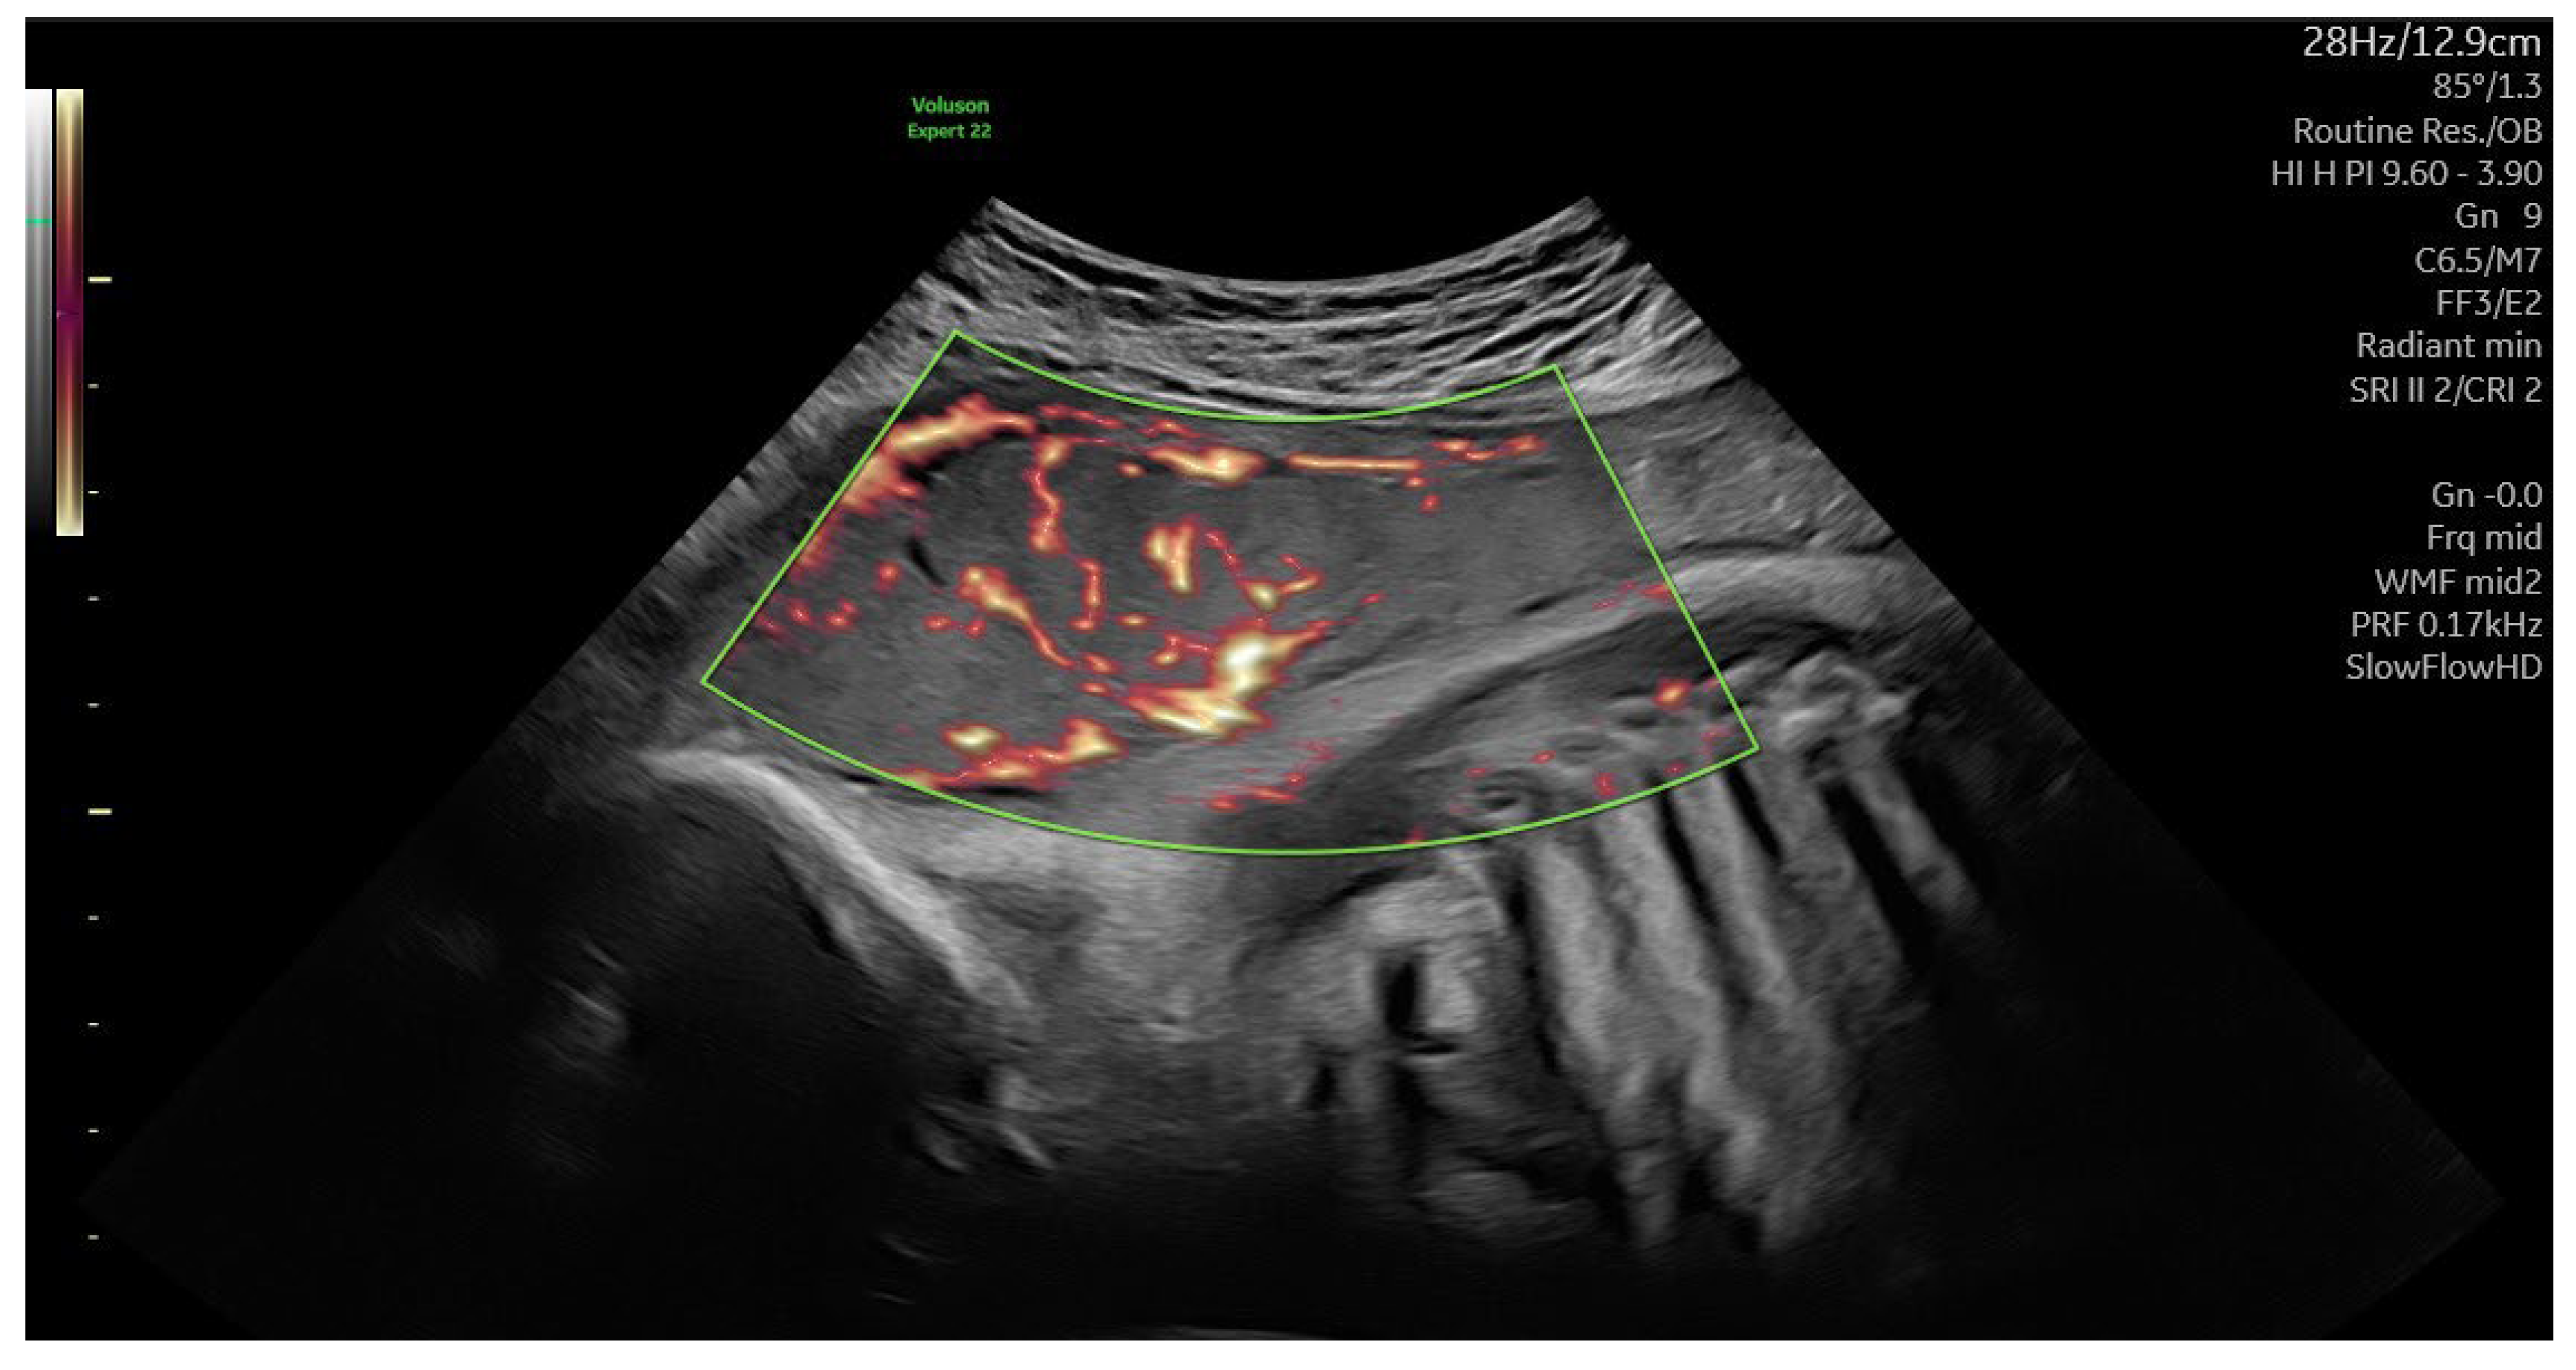

| Placental sonography | Normal BMI (N=30) | BMI>30 kg/m2 (N=12) | GDM (N=6) |

|---|---|---|---|

| Placental volume (ml ± SD) | 527.3 ± 93.1 | 775.6 ± 143.2 * | 754.6 ± 155.3 * |

| VI (mean ± SD) | 14.11 ± 5.1 | 8.71 ± 2.4* | 7.67 ± 3.3* |

| FI (mean ± SD) | 44.97 ± 22.64 | 37.4 ± 10.9 * | 39.4 ± 14.1 * |

| VFI (mean ± SD) | 8.21 ± 3.63 | 4.74 ± 1.34* | 3.99 ± 2.67* |